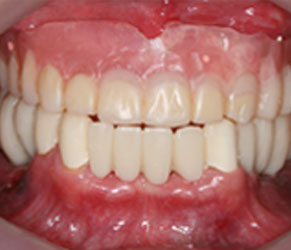

즉시 보철

잇몸을 절개하지 않고 임플란트를 식립하며, 당일에 보철이 가능합니다. (뼈 상태에 따라 치료기간이 길어질 수 있습니다.)

임플란트 수술 후 즉시 식사가 가능합니다.

치아가 없는 아랫부분에 네비게이션(가이드)임플란트로, 기존에 뺐다 꼈다 했던 불편한 틀니 대신 좀 더 음식을 잘 씹을 수 있는 임플란트로 진행하였습니다.